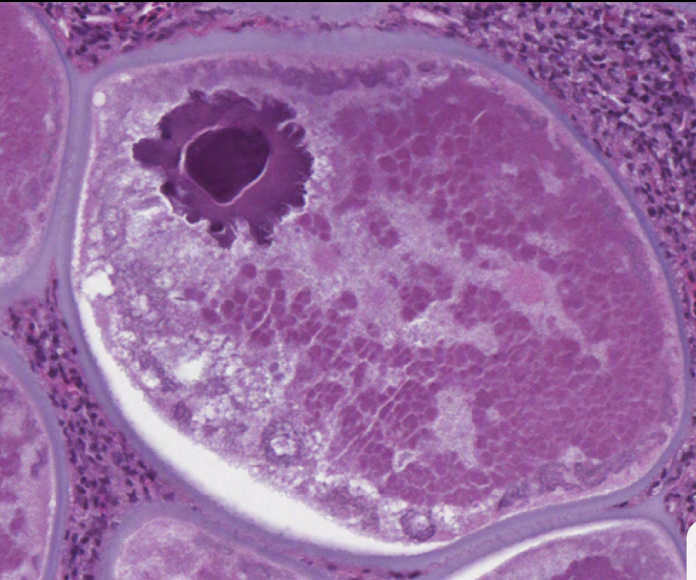

What is seen in this image? What is the large dark puple area in the upper left corner? What are the small dots surrounding the large cell?

This is a fibroblast with lymphocystis. It is up to a million times larger than normal. The fibroblast keeps growing and growing.

The small dots are the nuclei of normal sized cells. The large dark purple area is the nucleus of the infected cell.